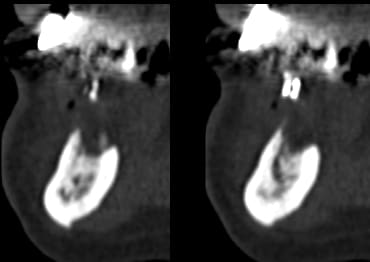

> La démo super bien menée sur un cas bcp plus difficile à gérer

> qu'il y paraissait

> Beaucoup de calme et de sureté et d'humour,dans les moments difficiles et il y

> en a eu, même avec la technique d'expansion condensation les 2 artérioles ont

> essayé de l'embêter, les tables vesti en regard 42 et 32 aussi

> au final 4 implants enfouis et bloqués

> travail très propre et j'ai beaucoup appris

mais je n'aurai du ecouter que mon coeur et en mettre un 5° en 33 ce serait plus joli sur le pano

Le pano pré-op est-il disponible ?

Il y avait des exo ?

C'est quoi le plan de tx pour la prothèse ?

Pourquoi expansion ?

Je crois que la disposition des implants est un peu étrange...